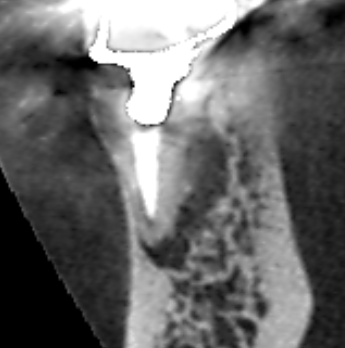

精密根管治療6カ月後の経過観察時の矢状断のCT画像です。下顎第一大臼歯の矢印の先にあった膿の影が消え、歯槽骨が再生しています。